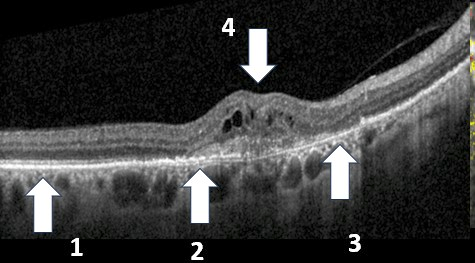

We concentrate on the fovea or the central part of the macula which normally is depressed on the OCT. Here the fovea is swollen from exudation and represents an elevation (4). To assess the vision, we concentrate on the posterior two layers of the retina and RPE. The photoreceptors or cells that transmit light to the retina occupy this space. In the left side of the photo, these layers are relatively normal (1), however in the fovea, the layers are markedly disrupted (2) and even missing (3). GA is present when the RPE is missing (3).